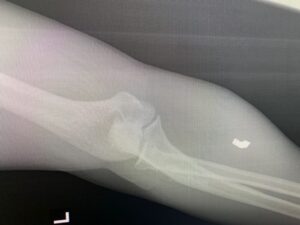

Over the last 3,000 years, combat has certainly changed, with a Trojan horse now referring to a method of electronic warfare rather than the legendary wooden decoy, however soldiers continue to experience peripheral nerve trauma from extremities that are not protected by modern body armor. While deployed I evaluated two patients injured in a 107mm Katyusha rocket attack who each sustained fragmentation injuries to the extremities (Figure 1 and 2). One patient had a large entrance wound in the right buttock with the fragment passing just posterior and lateral to the sciatic nerve, which could be palpated through the wound itself. The nerve was inspected and neurolysed, with only minor bruising present, and the patient maintained full function of the lower extremity. The other patient was injured in the same rocket strike, holding up his arms in a blocking fashion and had several fragments lodged in his upper extremities, the largest of which was removed from his forearm. Thankfully no nerve injuries were identified.